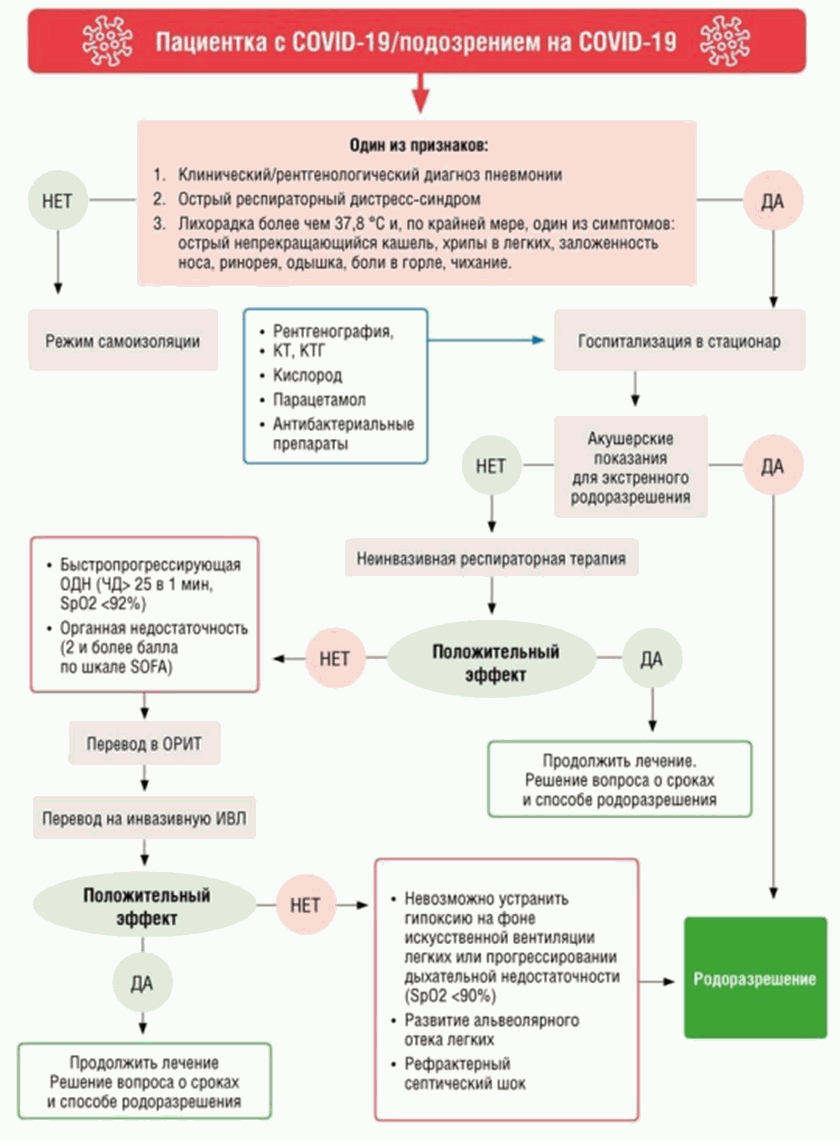

5. При наличии показаний госпитализация в стационар (см. приложение 1).

Алгоритм ведения беременных с подозрением или верифицированной инфекцией COVID-19